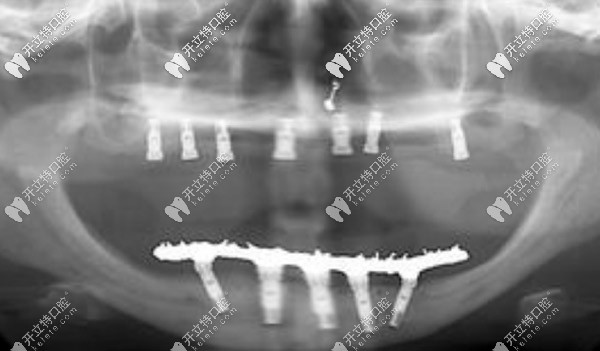

【全口allon4/6即刻負(fù)重技術(shù)】

一般需要8顆或12顆種植體,可恢復(fù)全口牙,當(dāng)然這個(gè)費(fèi)用比較高,韓系的價(jià)格一般在12萬元起。

滿口allon4/6即刻負(fù)重技術(shù)

種植牙的優(yōu)勢(shì)就不過多介紹了,ALLon4與普通的種植技術(shù)不同在于,利用斜拉式的力學(xué)原理,可以避免上頜竇及下頜神經(jīng)等危險(xiǎn)區(qū),當(dāng)天即可戴牙吃東西。美中不足則是該技術(shù)對(duì)醫(yī)生的技術(shù)要求較高,且費(fèi)用較高。